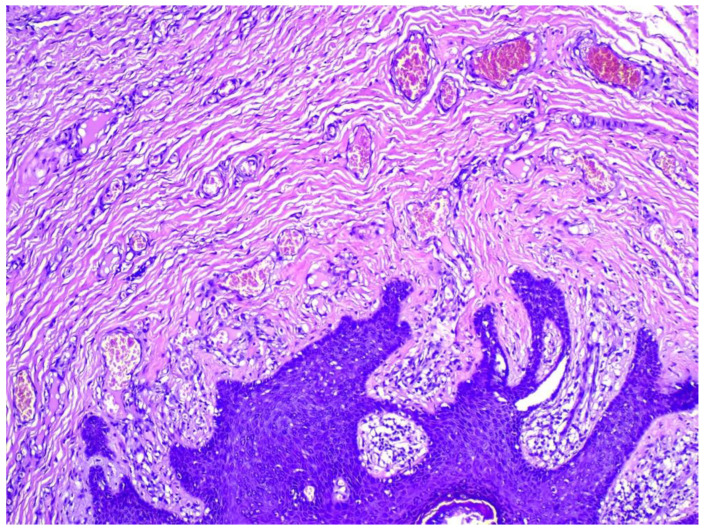

卵泡皮脂腺囊性错构瘤(FSCH)是一种罕见的错构瘤,通常表现为成人面部中央区域的无症状,孤立的圆顶状或带梗丘疹。我们报告一个35岁的女性谁提出了6个月的历史皮肤病变在她的大阴唇。组织学表现包括囊状扩张的毛囊,具有分支状上皮链和相互连接的皮脂腺,与FSCH的诊断一致。FSCH的生殖器变异在1998年首次被描述,从那时起,文献中只报道了6例。我们的目标是提高对这种罕见表现的认识,因为它具有重要的心理意义和误诊的风险。

Folliculosebaceous cystic hamartoma (FSCH) is an uncommon hamartoma that usually presents on the central face area of adults as an asymptomatic, solitary dome-shaped or pedunculated papule. We report a case of a 35-year-old female who presented with six-months history of skin lesions on her labia majora. Histological findings included cystically dilated hair follicles with branching epithelial strands and interconnecting sebaceous gland consistent with the diagnosis of FSCH. The genital variant of FSCH was first described in 1998 and since then only six cases have been reported in the literature. We aim to increase awareness of this rare presentation due to the significant psychological implications and the risk of misdiagnosis.